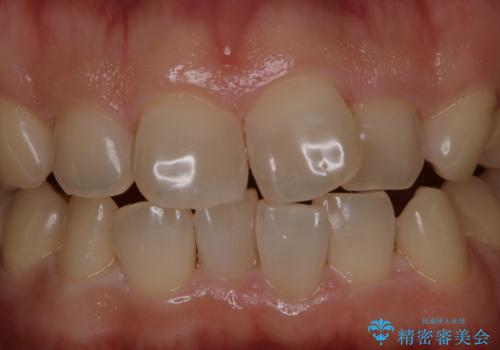

細かいステインをPMTCでOFF

- 歯ブラシをしてもとれないステインが気になるとのことで来院されました。PMTC60分コースを行いました。

PMTCは、歯に付着した汚れを除去していくため、着色が気になる場合にも行うことができます。ご自身でのセルフケアだけで着色を落とそうとすると、逆に歯を傷つけてしまったり、精密に汚れを除去できないこともあります。また、日常生活で着色しやすい飲食物を避けたりすることはストレスに感じてしまったり、あまり現実的ではありません。

毎日丁寧に歯磨きをしていても、日常生活での飲食物などにより着色してしまうことはあります。PMTCでは、歯の表面の凸凹にミネラルを補給して、ツルツルの表面に仕上げます